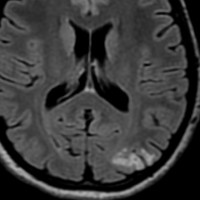

限局性のびまん性星細胞腫

無症状で発見された若年成人のびまん性星細胞腫,一つの脳回に限局するタイプでsingle gyrus gliomaといいます